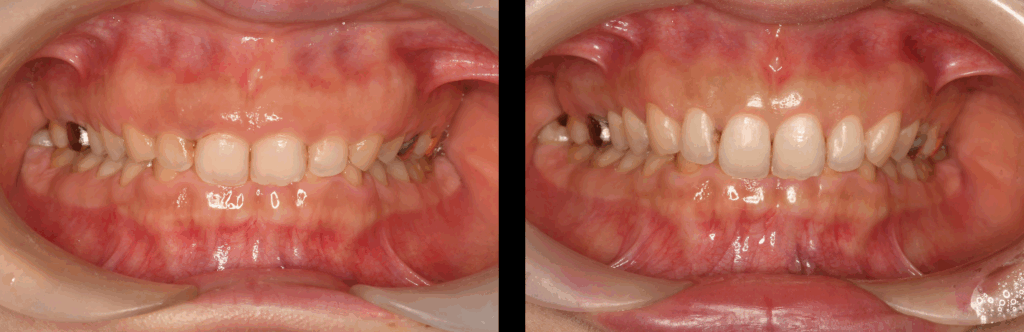

治療前

治療前後比